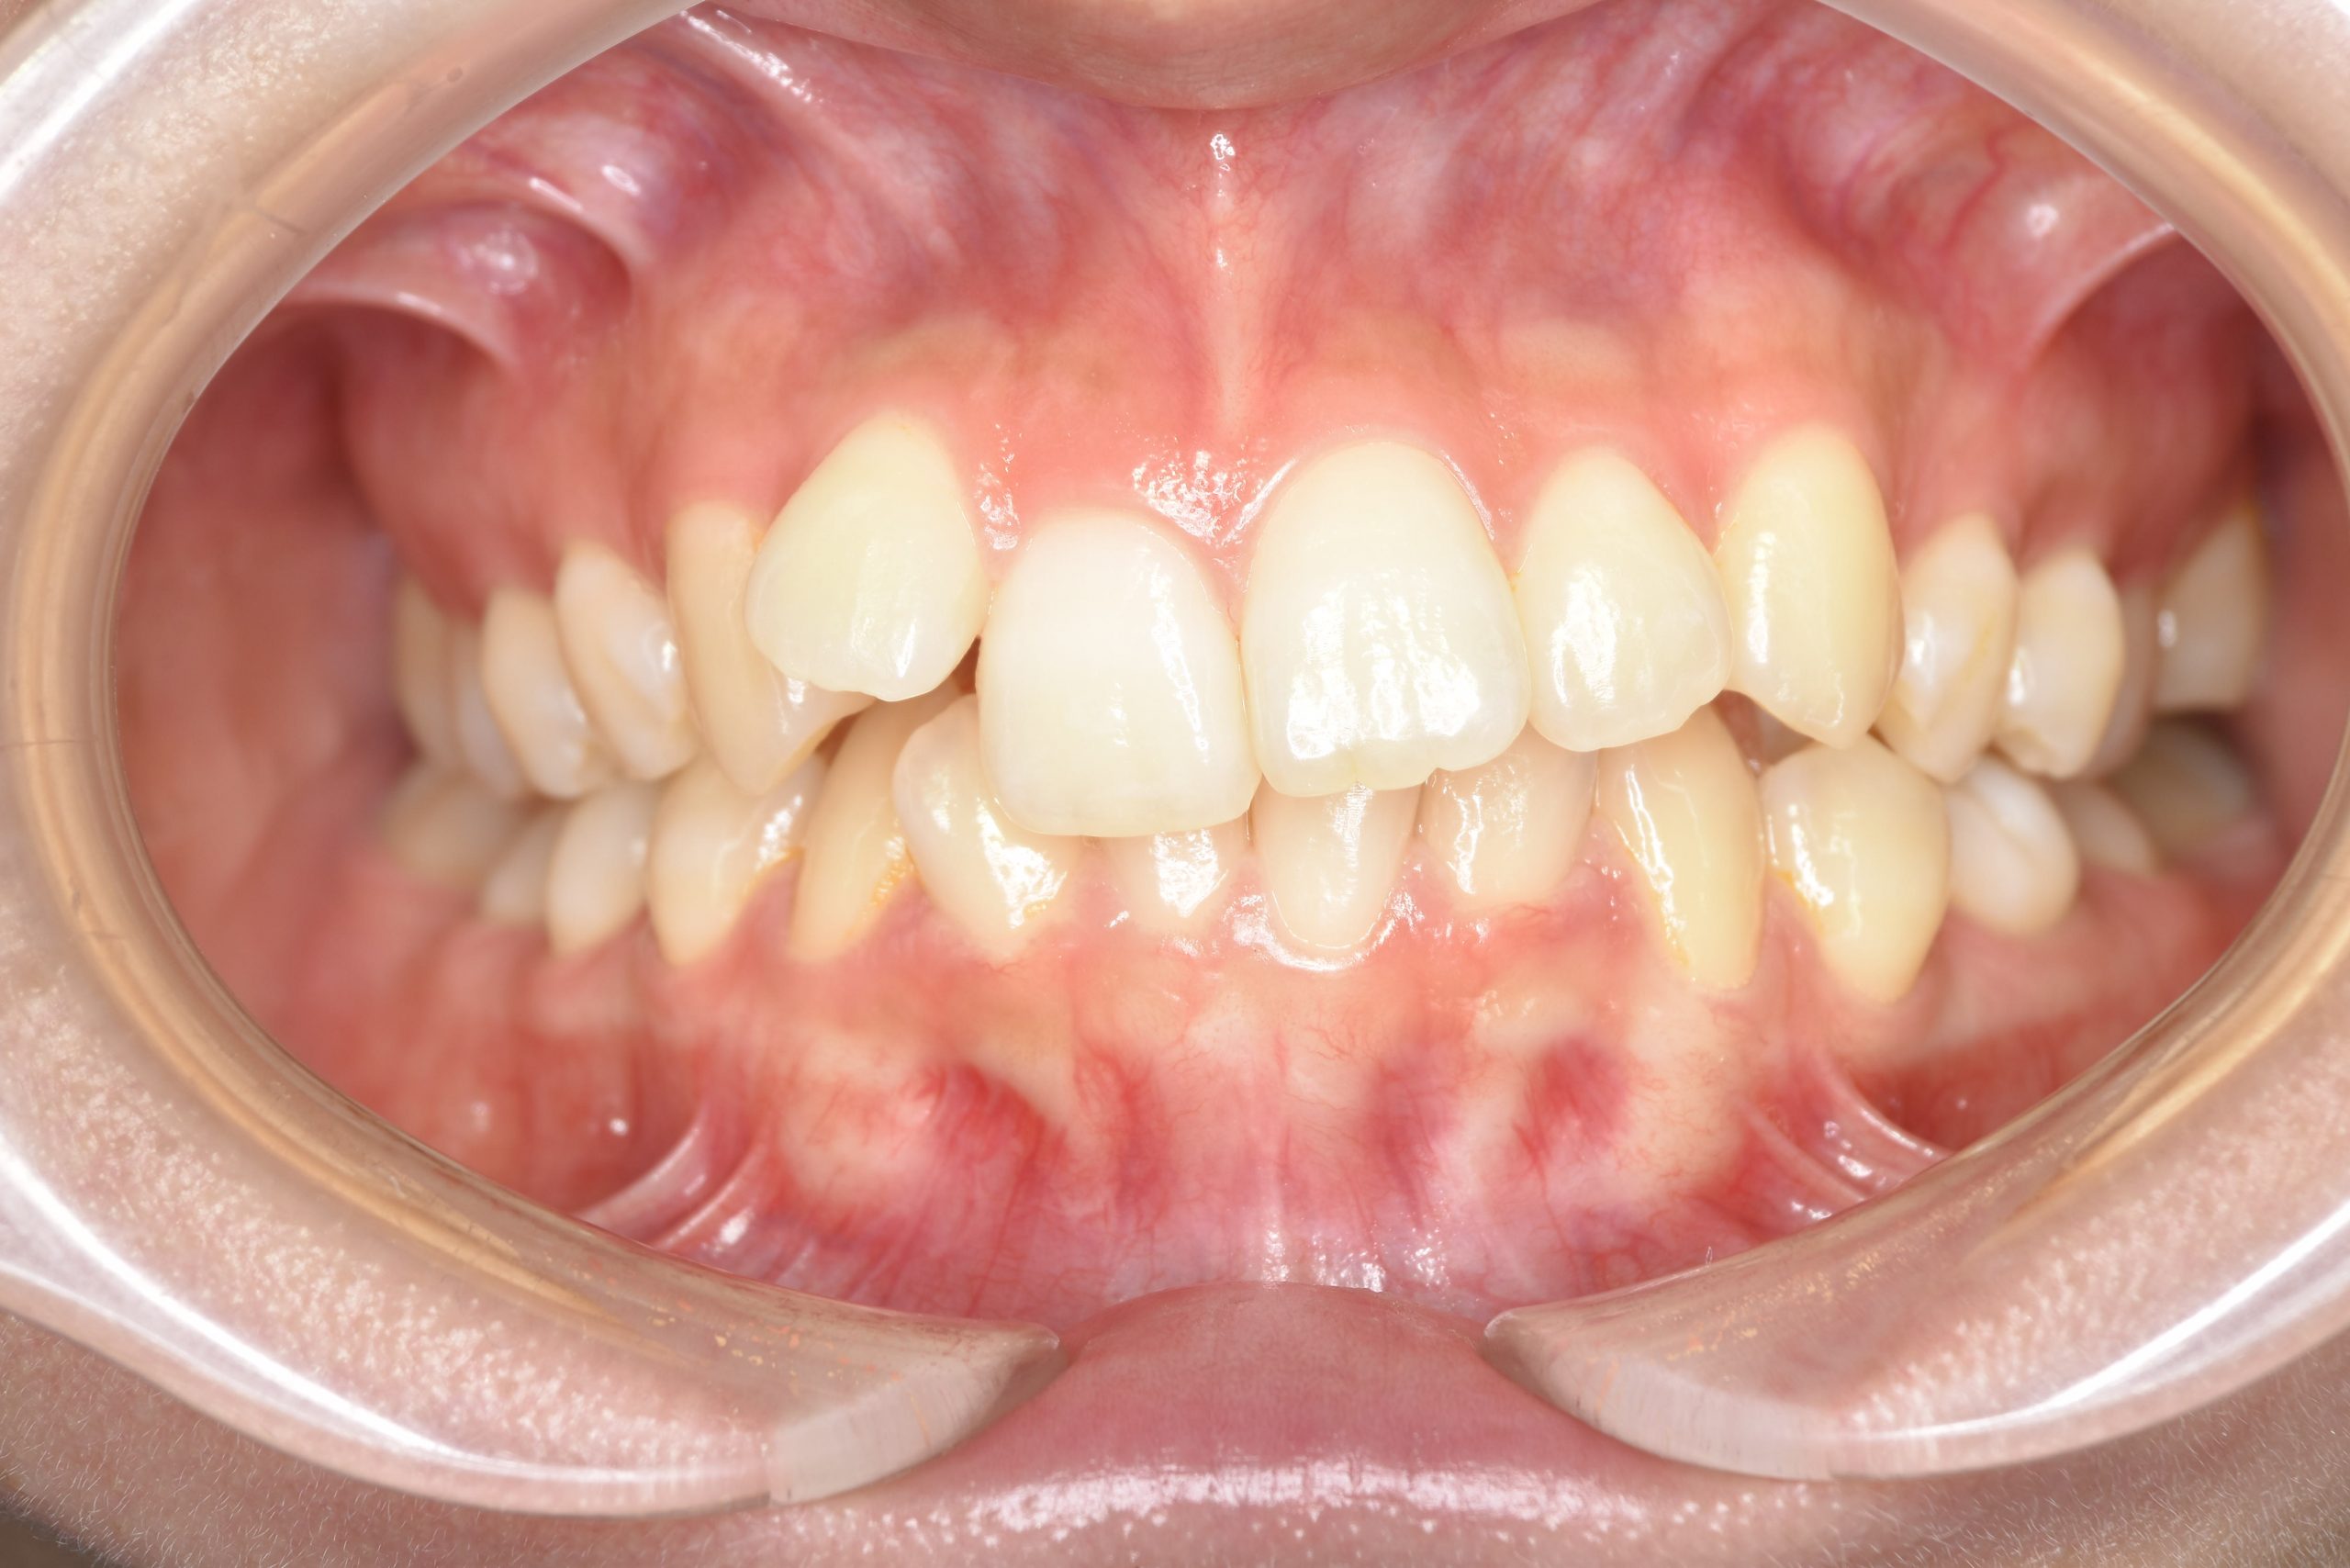

アフター

全顎ワイヤー矯正 症例_418

主訴 歯並びがガタガタ ※抜歯あり

施術内容 成人矯正1期治療

治癒期間 2年10か月間

費用 1,069,200円(税込)